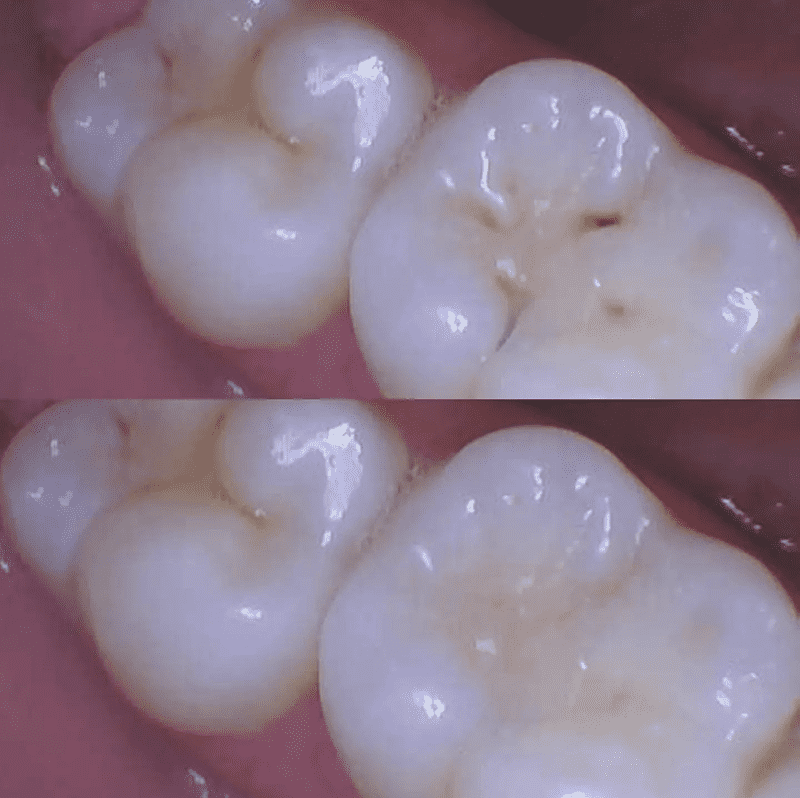

We offer state-of-the-art composite dental fillings in Leesburg, Virginia, as a core part of our comprehensive dental services. When cavities or tooth damage strike, composite fillings are a top-choice restorative solution, blending seamlessly with your natural teeth for both aesthetic and functional advantages.

- Aesthetic Appeal: These fillings are color-matched to your natural teeth, making them virtually indistinguishable. Say goodbye to unsightly metal fillings.

- A thorough examination by Dr. Kime Whitman to identify the extent of the decay or damage.

- Removal of the damaged tooth structure.

- Application of the composite material in layers, each one carefully cured to ensure a solid bond.

- A final shaping and polishing to create a seamless appearance.

- Natural appearance

- Long-lasting results